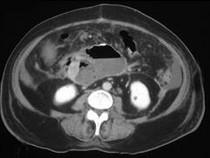

问题 女,33岁,发热,中上腹压痛反跳痛,血清淀粉酶增高,CT检查如图,最可能的诊断是 ( )

选项 A.急性胰腺炎 B.慢性胰腺炎 C.胰腺脓肿 D.胰腺假性囊肿 E.胰腺癌

答案 C